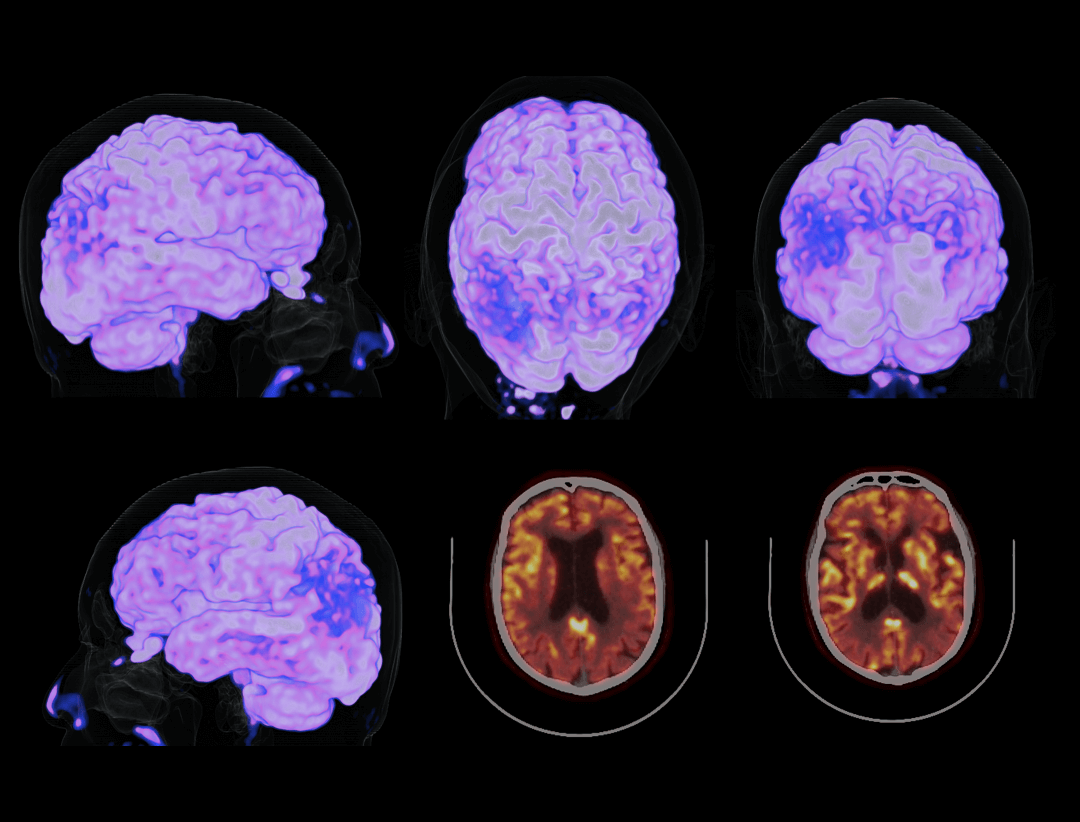

超清显像

600 x 600

超大矩阵,高精度超清重建